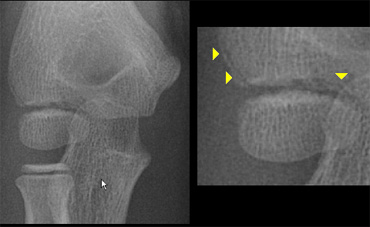

The diagnosis of a lateral condyle fracture can be challenging.

Fracture lines are sometimes barely visible (figure).

Remembering the fact that the lateral condyle fracture is the second most common elbow-fracture in children and because you know where to look for will help you

Lateral condyle fracture. On the x-ray only a small metaphyseal fragment is visible. The detatched fragment however is larger than it appears on the radiograph. The fracture extents into the lateral ridge of the trochlea. Elbow is probably unstable. Lateral condyle fracture. On the x-ray only a small metaphyseal fragment is visible. The detatched fragment however is larger than it appears on the radiograph. The fracture extents into the lateral ridge of the trochlea. Elbow is probably unstable.